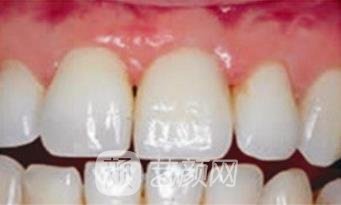

三、上海六院口腔科牙齿种植案例

小的时候没有刻意保护自己的牙齿,年龄超过40岁之后就发现了牙根松动的情况,有那么一两颗牙松动的比较厉害,干脆选择把牙齿拔掉做了种植,经过修复之后的牙齿,相对来说还是比较稳固的,用了有半年的时间进行恢复,已经没有不舒服的感觉。